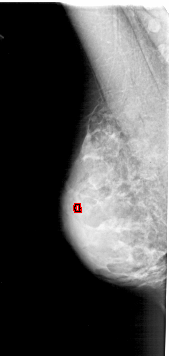

FILE: A_1775_1.LEFT_MLO.OVERLAY

TOTAL_ABNORMALITIES 1

ABNORMALITY 1

LESION_TYPE CALCIFICATION TYPE PLEOMORPHIC DISTRIBUTION CLUSTERED

ASSESSMENT 4

SUBTLETY 1

PATHOLOGY BENIGN

TOTAL_OUTLINES 1

BOUNDARY